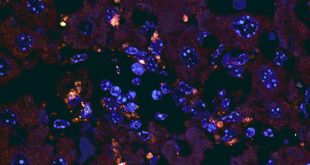

Read More »Study: Gut Bacteria Trigger Autoimmune Disease

Enterococcus gallinarum, a species of bacterium found in the small intestines of humans and mice, can travel to other organs and trigger an autoimmune response, according to a new study published in the journal Science. The findings suggest new approaches for treating chronic autoimmune conditions, including systemic lupus and autoimmune …